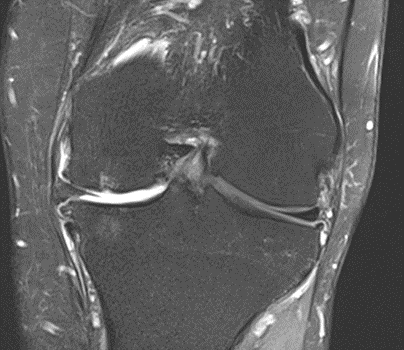

MRI scans illustrating the improvements regarding Group 2 are presented below, showing pre-treatment images with evident cartilage defects, pronounced bone marrow edema, and synovial inflammation, followed by post-treatment scans demonstrating improved joint structure, reduced edema, and decreased inflammation (Figures 12-29).

Figure 14: Male, 78 years, pre-intervention MRI.

Figure 15: Male of figure 14, two-month follow-up MRI: MSC plus ChondroFiller® liquid.